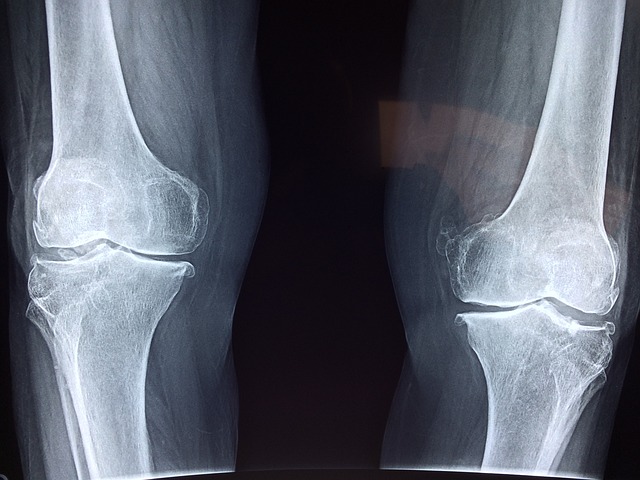

콘드로이친은 우리 몸의 연골 조직에서 자연적으로 발견되는 물질입니다. 주로 연골을 구성하는 주요 성분 중 하나이며, 관절의 윤활 작용을 돕고 염증을 줄이는 데 중요한 역할을 합니다. 이러한 특성 덕분에 많은 사람들이 관절 건강을 위해 보충제로 섭취하고 있습니다.